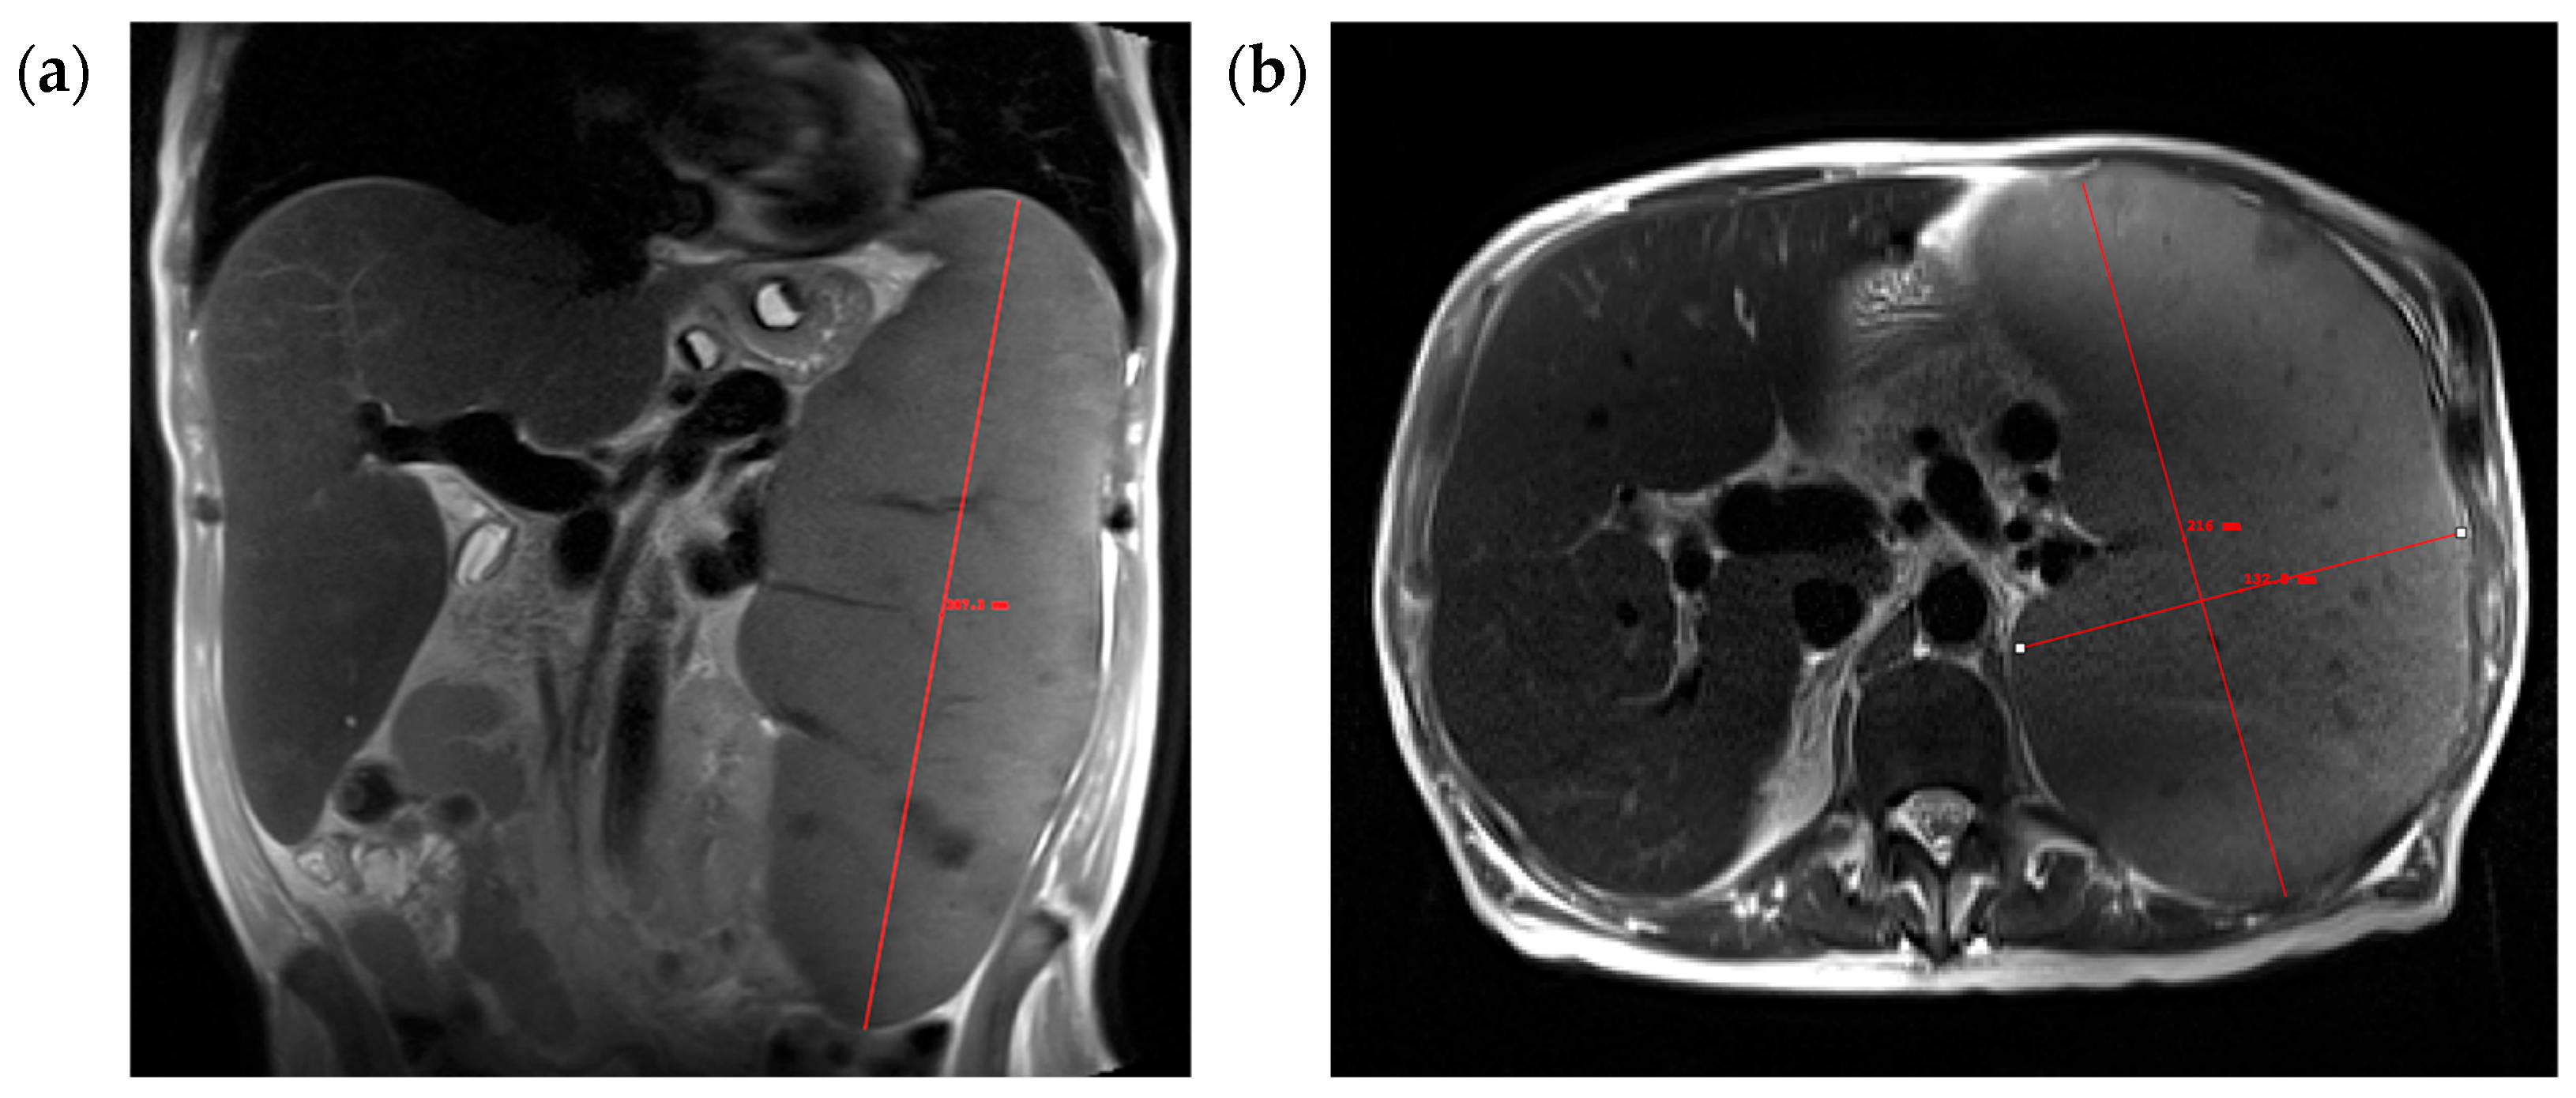

2. Materials and Methods

2.4. Spleen Volume Measurements